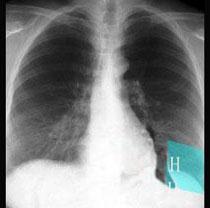

问题 在图所示正常胸部X线影像图像上,该英文字母所代表的肺段为 ( )

选项 A、H代表后基底段 B、H代表背段 C、H代表前基底段 D、H代表外基底段 E、H代表内基底段

答案 D